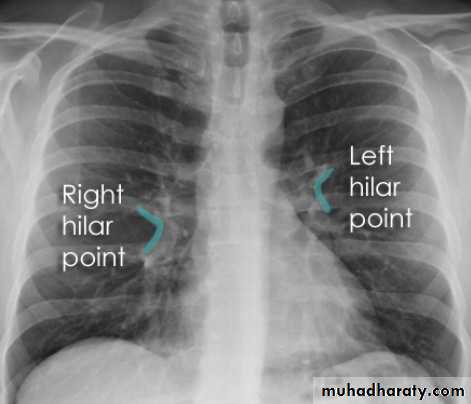

Hilar structuresThe hila (lung roots) are complicated structures mainly consisting of the major bronchi and the pulmonary veins and arteries. These structures pass through the narrow hila on each side and then branch as they widen out into the lungs. The hila are not symmetrical but contain the same basic structures on each side.

Key points

Each hilum contains major bronchi and pulmonary vessels

There are also lymph nodes on each side(not visible unless abnormal)

The left hilum is often higher than the right

Both hila should be of similar size and density. If either hilum is bigger and more dense, this is a good indication that there is an abnormality.